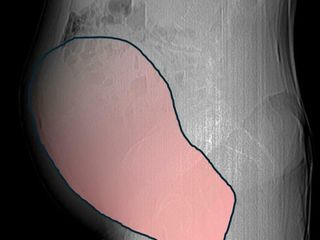

Per mesi la gigantesca cisti ovarica, con un diametro di circa 28 centimetri, è rimasta nascosta, senza dare segnali evidenti. La paziente non si era accorta di nulla. L’allarme è scattato quando la massa, associata alla presenza di una seconda neoplasia intestinale, ha iniziato a comprimere il colon, provocando sintomi acuti ed improvvisi fino ad una grave difficoltà intestinale non più ignorabile.

Fondamentale in questa fase il contributo della Radiologia dell'ospedale Sant’Anna, che fornisce l’imaging preoperatorio indispensabile per affrontare un quadro clinico di eccezionale complessità.

Durante l’intervento emerge tutta la gravità della situazione. La gigantesca neoplasia ovarica viene asportata: pesa circa 6 chilogrammi, con un volume paragonabile a quello di una gravidanza gemellare a termine. Ma non è l’unica minaccia. I sintomi più pericolosi sono legati alla sofferenza intestinale, che richiede un intervento immediato e coordinato di più specialisti.